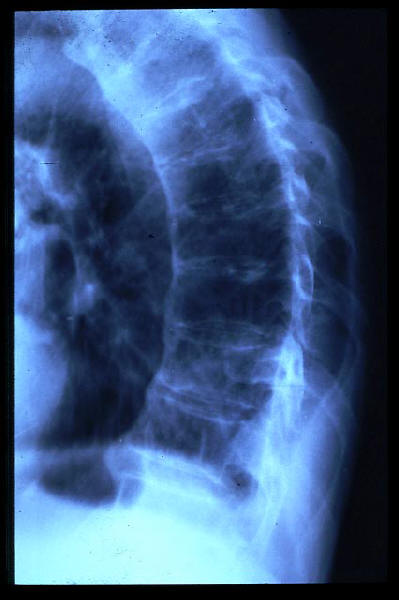

Osteoporosis. Cifosis.